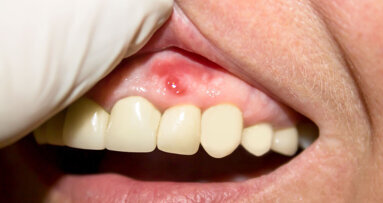

Un uomo di 21 anni si presenta con un importante disturbo dovuto a una ricaduta di un trattamento ortodontico effettuato durante l’adolescenza. Ha ...